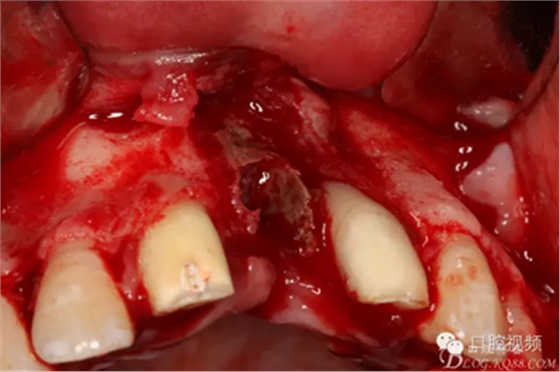

圖8.切開、翻瓣、完整暴露壞死部分牙槽骨

圖9.牙槽骨壞死達(dá)鼻底